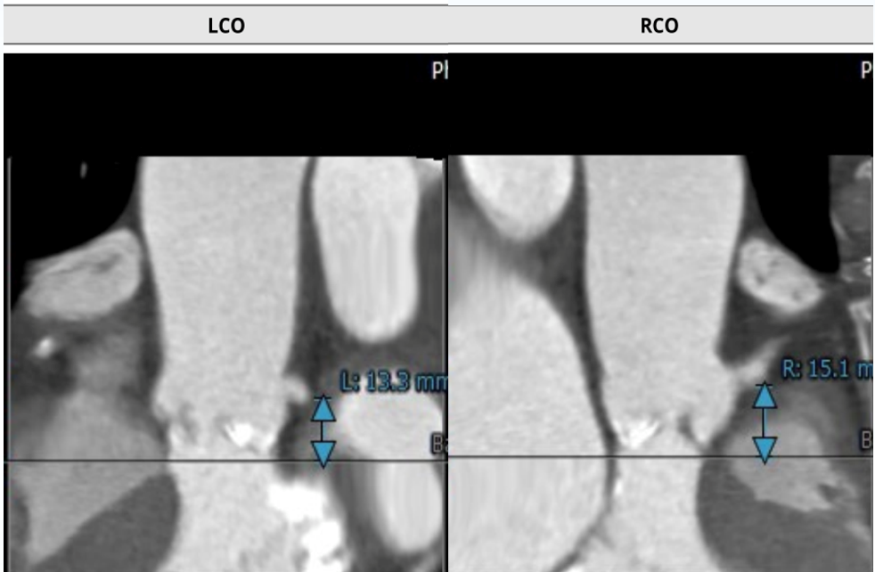

该名患者为三叶瓣,右冠窦轻度钙化。瓣环直径为23.2mm,周长为72.9mm。左冠窦中重度钙化。升主动脉稍增宽,平均直径34.0mm。左冠开口高度13.3mm,右冠开口高度15.1mm,冠脉风险低。外周血管钙化轻,入路情况较佳。

冠脉开口